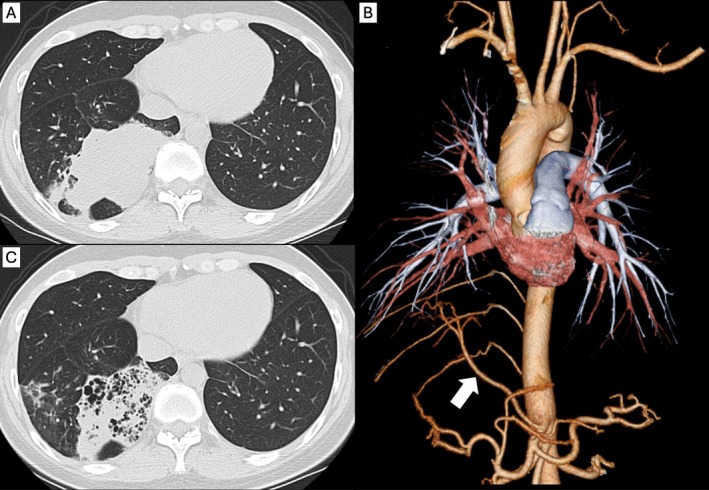

摘要先天性肺气道畸形(CPAM)是一种罕见的成人先天性肺异常,有恶性转化的危险。伴有全身血供异常的CPAM病变被认为是混合型病变(HL)。成人患HL的病例很少。在这里,我们报告了一位44岁的女性,她表现为血清碳水化合物抗原19-9 (CA19-9)水平升高,并被诊断为HL,伴有腹腔动脉异常动脉血流。手术切除后,血清CA19-9水平立即降至正常范围。切除肺组织免疫组化染色显示细支气管纤毛柱状上皮细胞CA19-9阳性。本报告强调,即使在没有恶性肿瘤的情况下,HL患者血清CA19-9水平也可能升高。

Congenital pulmonary airway malformations (CPAM) are rare congenital pulmonary anomalies in adults and are at risk of malignant transformation. CPAM lesions with abnormal systemic blood supply are considered hybrid lesions (HL). There are few cases of HL in adults. Here, we report a 44-year-old woman who presented with elevated serum carbohydrate antigen19-9 (CA19-9) levels and was diagnosed with HL with abnormal arterial blood flow from the celiac artery. After surgical resection, serum CA19-9 levels immediately decreased to the normal range. Immunohistochemical staining of the resected lung tissue showed positive staining for CA19-9 in the bronchiolar ciliated columnar epithelial cells. This report highlights that elevated serum CA19-9 levels may be seen in HL, even in the absence of malignancy.